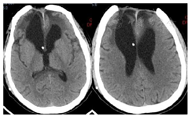

头颅CT(图1)提示:双侧额叶脑挫裂伤并出血术后状态;颅骨CT三维成像(图2)提示:额骨骨质缺损,额窦壁、右侧眼眶内壁、上颌窦壁等多处骨折。脑脊液检查结果:葡萄糖<1.0 mmol/L,乳酸5.62 mmol/L,氯106.7 mmol/L,蛋白质1.19 mmol/L,白细胞计数(white blood cell count,WBC)83×106/L。

患者于伤后当天(2021年7月29日)在当地医院急诊行"颅内血肿清除术+凹陷性粉碎颅骨骨折清除术",术后持续出现脑脊液鼻漏,伴伤口渗液,持续昏迷,GCS评分E1VTM3。患者于2021年8月3日转入我院,于2021年8月5日在全麻下行"颅骨骨折整复+脑脊液漏修补术",开颅探查前颅底进行重建修补,额窦及筛窦存在裂缝,封填额窦和筛窦,并取大腿部部分阔筋膜、少量脂肪和肌肉填塞,术中见额部硬膜存在缺损,以人工脑膜进行严密缝合,留置皮下引流管,术后第3天引流量少,皮下引流管拔除。术后观察患者未再出现脑脊液漏。术后仍为昏迷状态,住院期间,间断出现发热,热型表现为不规则热。2021年8月8日行腰椎穿刺术并留取脑脊液检查,提示:WBC:83×106/L,葡萄糖<1.0 mmol/L,乳酸5.62 mmol/L,氯106.7 mmol/L,蛋白质1.19 mmol/L;脑脊液培养结果为:鲍曼氏不动杆菌;痰涂片可见革兰阳性球菌、阴性杆菌;考虑颅内感染并呼吸道感染。根据药敏结果给予以替加环素100mg、每12小时1次,联合万古霉素1.0g、每12小时1次抗感染治疗。患者仍存在持续高热,2021年8月10日行"腰大池置管外引流术",有黄色透明脑脊液流出,复查脑脊液结果提示:WBC:37×106/L,蛋白质1.18 mmol/L。2021年8月12日呼吸道标本培养提示:鲍曼氏不动杆菌,调用抗生素为多黏菌素50u、每12小时1次,联合替加环素100mg、每12小时1次,利奈唑胺600mg、每8小时1次,治疗呼吸道感染及预防革兰阳性球菌所致颅内感染。2021年8月16日患者意识呈昏迷状态,刺激能睁眼,体温间断高热,腰大池引流不通畅给予拔除。头部伤口愈合差,有少量脓性渗出,若进一步发展,有加重颅内感染可能,头部伤口给予留置VSD(图3)辅助伤口愈合。抗生素应用方案为多黏菌素50u、每12小时1次,替加环素100mg、每12小时1次,利奈唑胺600mg、每8小时1次。2021年8月17日复查脑脊液结果提示:WBC:350×106/L,蛋白质2.37 mmol/L,2021年8月19日患者呈浅昏迷状态,刺激可睁眼,患者痰培养、血培养、伤口分泌物培养均未见菌种生长,停用替加环素。体温较前稳定,感染基本控制。2021年8月24日复查脑脊液结果提示:WBC:8×106/L,蛋白质0.7 mmol/L,细菌培养未检出。查血清G试验结果为阴性GM试验<0.5 µg,肺泡灌洗液细菌培养未见菌种生长。复查头部CT示双侧额叶出血及水肿较入院时吸收,硬膜下少量积液(图4)。患者意识状态较前改善,回当地医院继续康复及支持治疗。